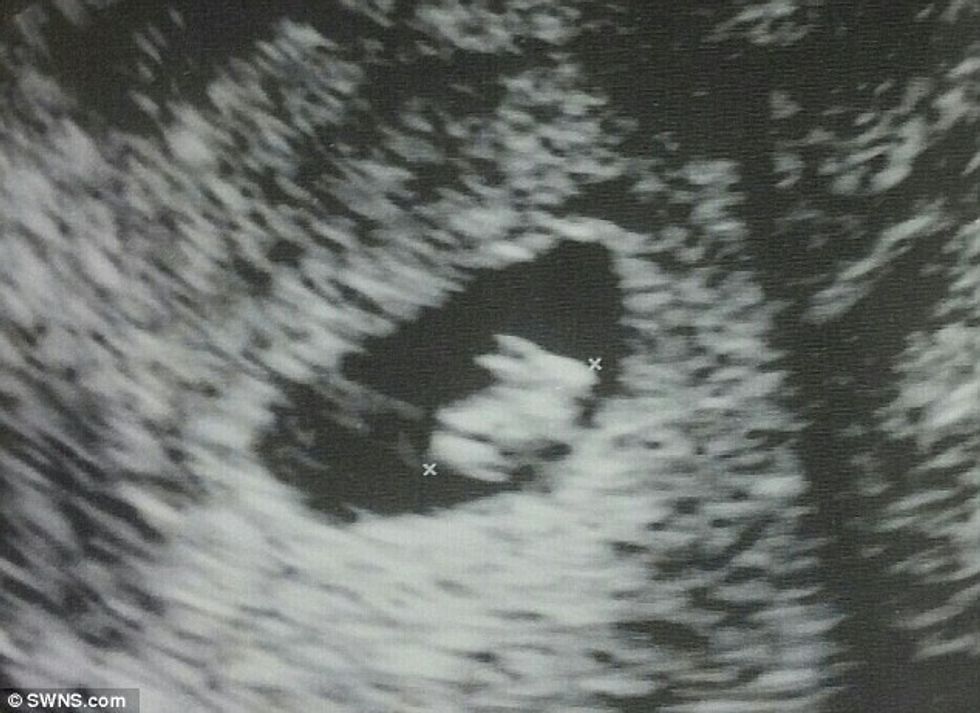

Fotografia bizare e ultrazërit, shfaqet një ‘lepur’ në vend të fëmijës (Foto)

Një nënë e ardhshme nga Florida e Shteteve të Bashkuara, është mahitur në rrjetin social Redit se mbanë në bark një lepur.

Shtatzëna 33-vjeçare, që nuk ka dashur të identifikohet, e ka postuar imazhin ku shihet brejtësi veshgjatë që ka katër këmbë, transmeton Telegrafi.

“Shkova për herë të parë për të bërë ultrazërin dhe doli se do ta lindi një lepur”, ka shkruar ajo përbri fotografisë.

Mësohet se fetusi që është në javën e shtatë, ka një formë normale dhe është i shëndoshë, ndërsa kjo pamje komike që është zënë rastësisht nga njëri kënd. /Telegrafi/